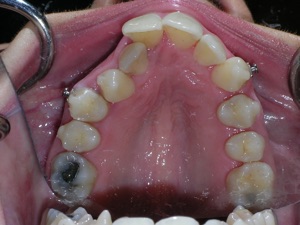

This case was of a young lady who desperately wanted Invisalign, but had been told it was not possible. There was not one, but two teeth that had come in toward the roof of the mouth.

Here are some progress photos.